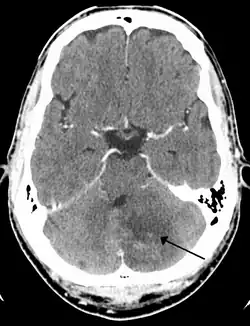

Left sided cerebellar stroke due to occlusion of a vertebral artery

Cerebellar strokes account for only 2-3% of the 600,000 strokes that occur each year in the United States.[3] They are far less common than strokes which occur in the cerebral hemispheres. In recent years mortality rates have decreased due to advancements in health care which include earlier diagnosis through MRI and CT scanning.[4] Advancements have also been made which allow earlier management for common complications of cerebellar stroke such as brainstem compression and hydrocephalus.[4]